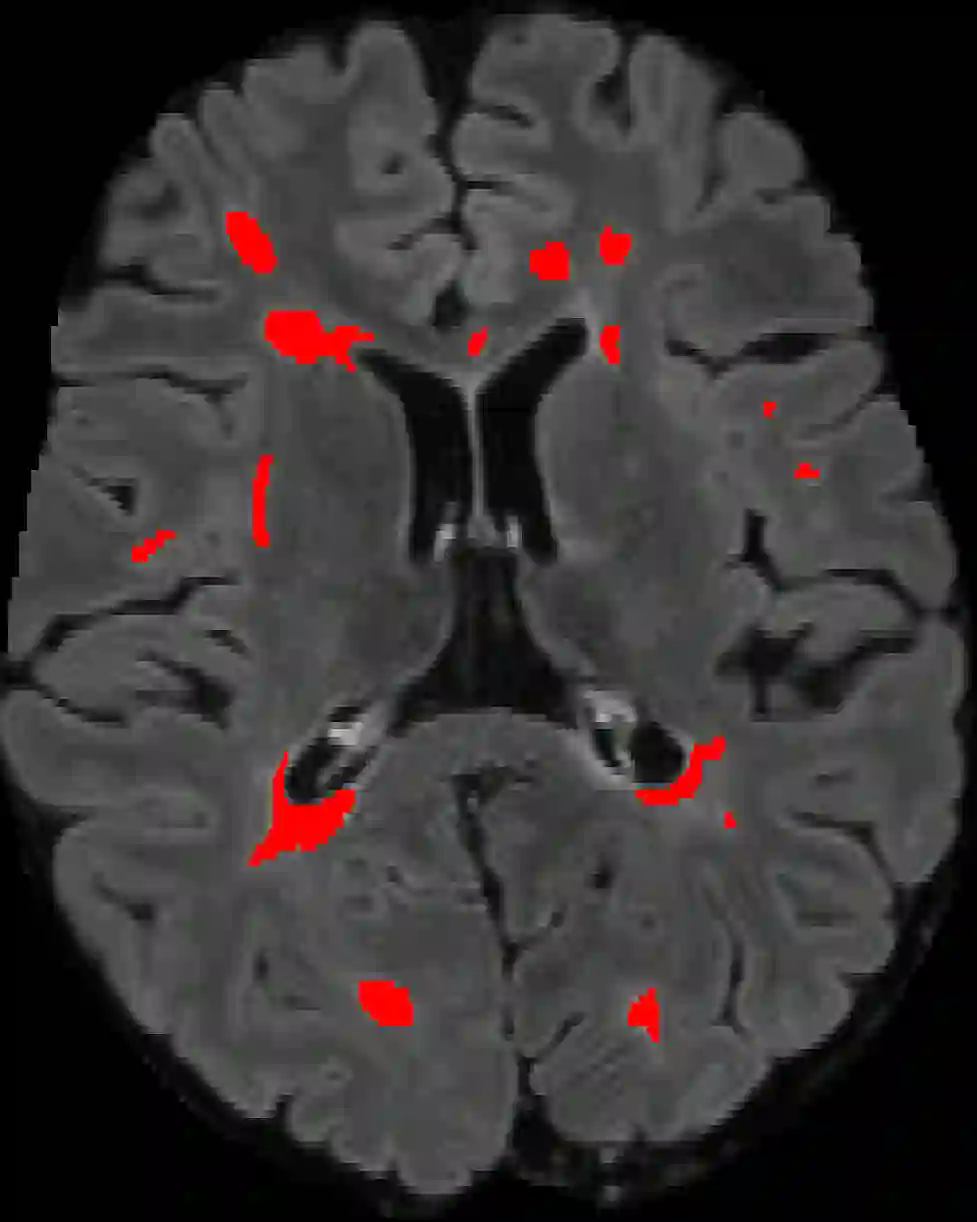

Assessment of lesions and their longitudinal progression from brain magnetic resonance (MR) images plays a crucial role in diagnosing and monitoring multiple sclerosis (MS). Machine learning models have demonstrated a great potential for automated MS lesion segmentation. Training such models typically requires large-scale high-quality datasets that are consistently annotated. However, MS imaging datasets are often small, segregated across multiple sites, with different formats (cross-sectional or longitudinal), and diverse annotation styles. This poses a significant challenge to train a unified MS lesion segmentation model. To tackle this challenge, we present SegHeD, a novel multi-dataset multi-task segmentation model that can incorporate heterogeneous data as input and perform all-lesion, new-lesion, as well as vanishing-lesion segmentation. Furthermore, we account for domain knowledge about MS lesions, incorporating longitudinal, spatial, and volumetric constraints into the segmentation model. SegHeD is assessed on five MS datasets and achieves a high performance in all, new, and vanishing-lesion segmentation, outperforming several state-of-the-art methods in this field.